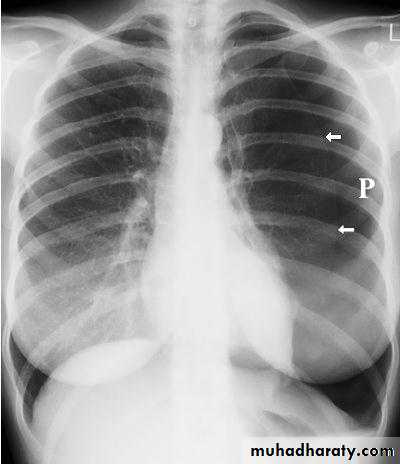

Case 1A 28 years old previously healthy female presented with sudden onset of localized right sided chest pain and feeling of shortness of breath.

OE: looks in pain, RR 22, PR 125. normal BP and Temp.

CXR shown

case 1

The chest X-ray shows thesharply defined edge

of the deflated lung with

complete translucency

(no lung markings)

between this and the

chest wall.